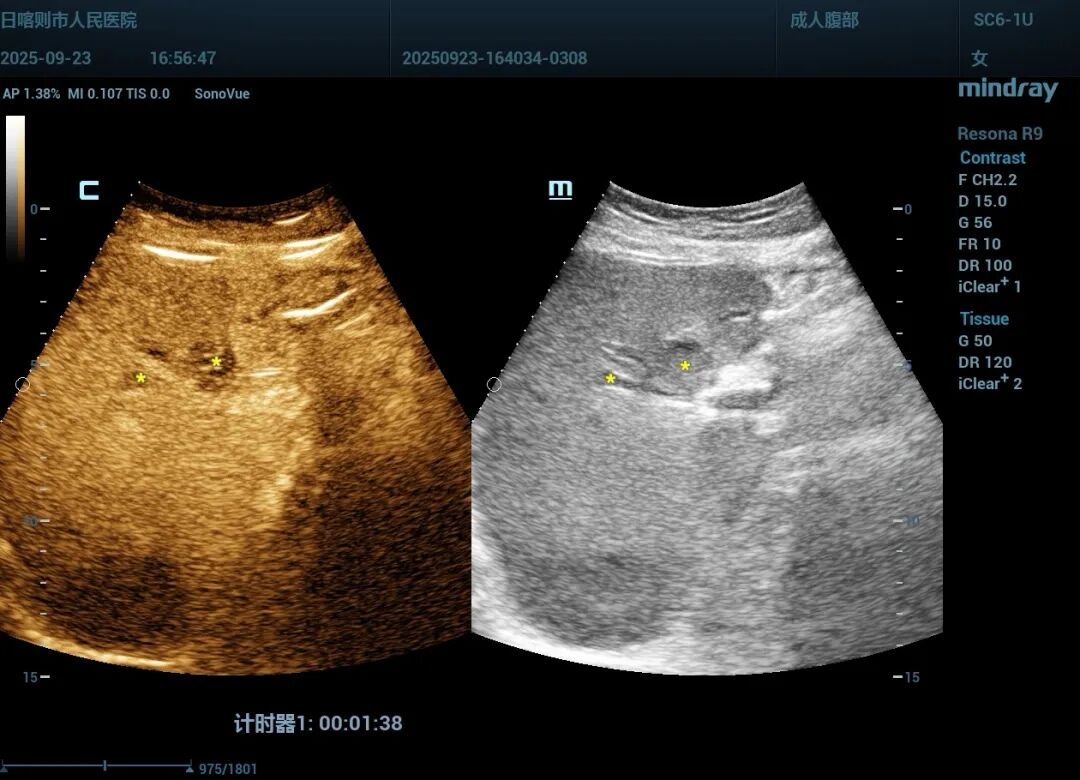

消融前超声造影定位病灶位置(左);消融后造影复查病灶完全破坏呈“黑洞征”(右)